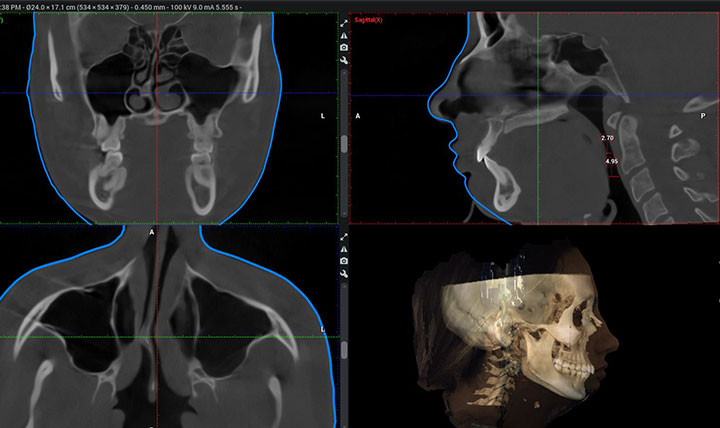

The Steinbacher Plastic Surgery Center is a highly regarded medical facility in Guilford, CT, known for providing exceptional care and achieving excellent results. The center specializes in various procedures, including jaw surgery, cosmetic surgery, asymmetry correction, and revision rhinoplasty. The skilled surgeon, Dr. Steinbacher, is renowned for his extensive knowledge, expertise, and compassionate approach, ensuring patients feel comfortable and confident throughout their treatment. Patients have shared positive experiences, noting the surgeon's professionalism, eye for aesthetics, and clear explanations that address their concerns effectively. The friendly staff is well-regarded for their excellent anesthetic care and prompt responses to patients' questions, creating a welcoming environment. Many patients have expressed their satisfaction with the natural, balanced results achieved by Dr. Steinbacher, who prioritizes patient satisfaction and strives for outstanding outcomes.